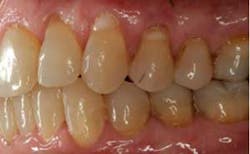

SFOT was used with a high-tech clear aligner to address hard- and soft-tissue deficiencies and severe maxillary and mandibular arch constriction.

A healthy, 57-year-old female presented with a lifelong desire for healthy, straight teeth and a beautiful smile. She had been told numerous times that it was not possible without premolar extractions.

SFOT surgery was performed in the maxillary and mandibular arches with deep buccal corticotomies. Particulate, demineralized, freeze-dried bone allograft and acellular dermal matrix were used to augment the ridges.

Total treatment time: 6 months. Patient declined recommended further clear aligner refinement and fine-tuning periodontal plastic surgery.